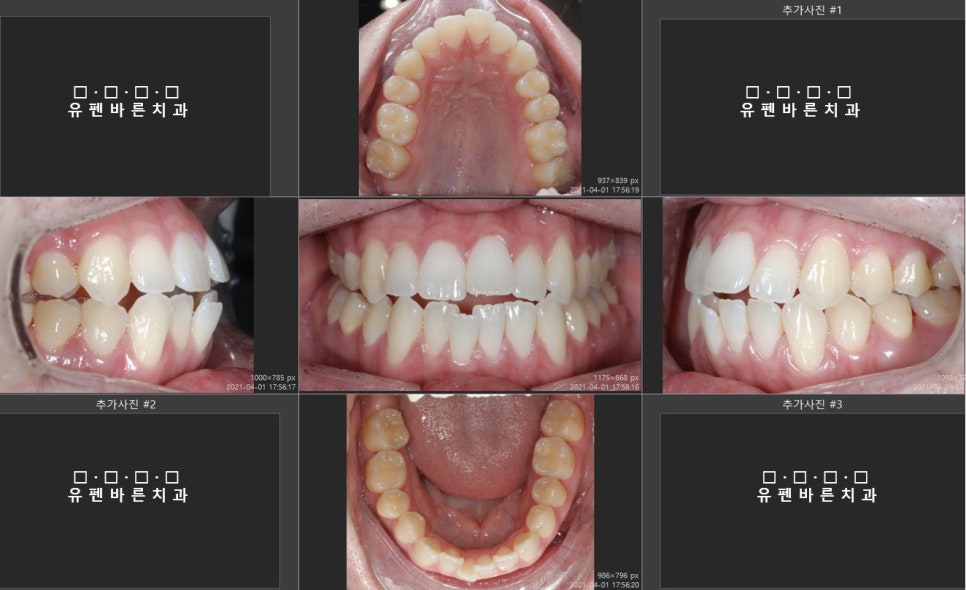

What would you choose? 안녕하세요 ^^ 유펜바른치과입니다. 때는 올해 4월경! 유펜바른치과에 미국 뉴욕에서 오신 외국인 환자분께서 잠실새내역교정 상담을 위해 방문해 주셨어요. 먼저 정확한 교정진단을 위해 구강내 사진을 찍어보았습니다 :) 어금니를 끝까지 다무신것 같은데.. 위...

먼저

정확한 교정진단을 위해

구강내 사진을

찍어보았습니다 :)

어금니를 끝까지

다무신것 같은데..

위, 아랫니 사이의 공간

보이시나요?

진단을 해보니

외국인 환자분의

치아 상태는

앞니끼리 물리지 않는

'개방교합(Open Bite)'

상태셨어요 ㅠ_ㅠ

사실

정상교합은

윗니가 아랫니를

2-3mm정도

덮고 있어야 하는데 말이죠..